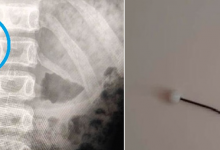

Иглу и клок волос извлекли из кишечника подростка в Актау

Игла расположилась таким образом, что не повредила кишечник девочки.